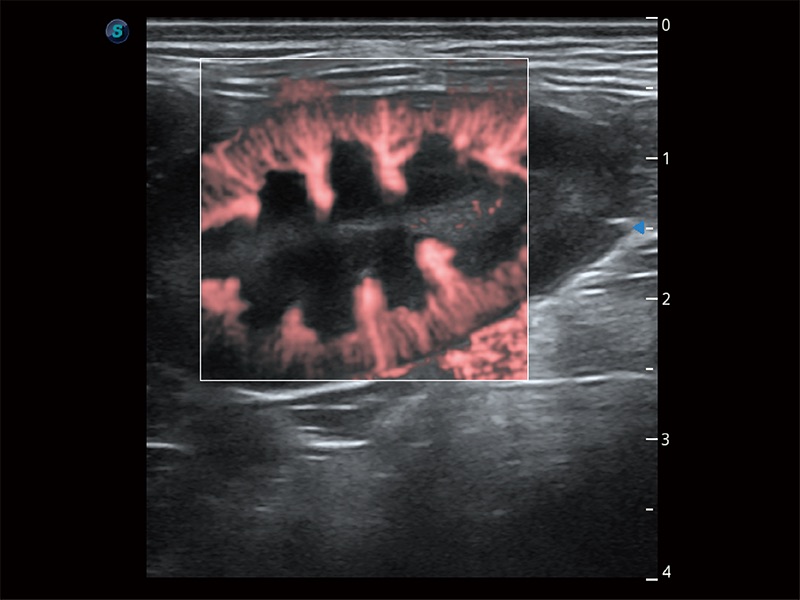

操作簡便,無需高頻度外力作用即可真實(shí)反映組織的形變,快速評估腫瘤良惡性。